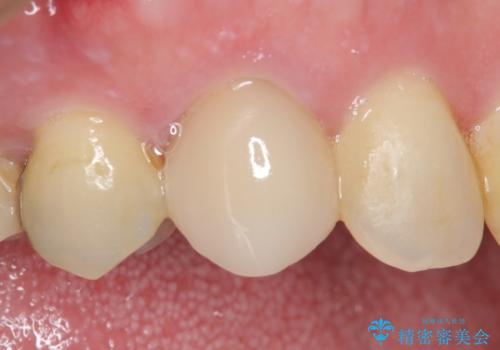

オールセラミッククラウン(スペシャル) 根管治療後の補綴

- 他院にて根管治療を行ったが疼きが治まらないため、当院にいらっしゃった方の症例です。

再根管治療を行い症状が治まったのを確認後、オールセラミッククラウン(スペシャル)による補綴を行いました。

- オールセラミッククラウン(スペシャル)…¥130,000、仮歯…¥10,000、ファイバーコア…¥20,000、精密根管治療費別途費用は治療当時の料金となります